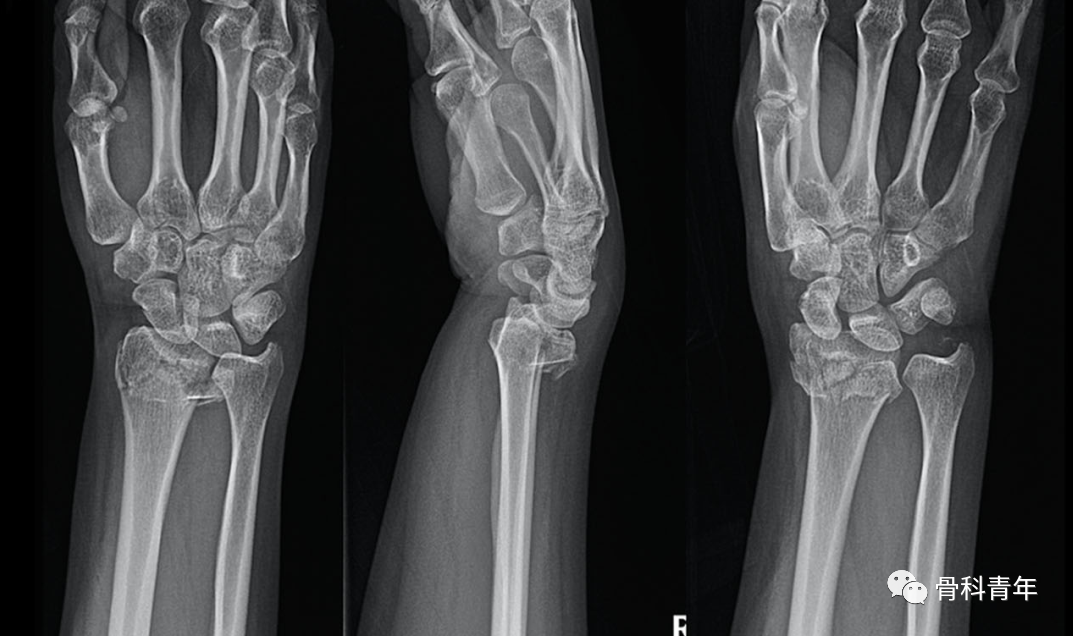

髓内钉技术广泛应用于长骨骨干骨折,闭合或有限切开复位有效降低医源性因素对血运的破坏,并具有良好的轴心固定生物学优势。桡骨远端髓内钉出现较晚,该技术适用于完全关节外骨折及简单的关节内骨折,对关节内粉碎骨折并不适用。

桡骨远端骨折髓内钉固定的前提是闭合复位效果满意,克氏针临时固定后,通过桡骨茎突开口,自腕背侧第1/2间室间隙进入。该技术存在潜在的损伤包括桡神经分支损伤,螺钉穿入下尺桡关节或桡腕关节等。